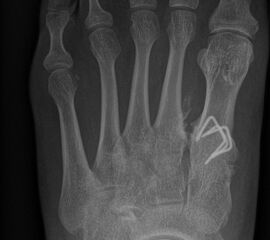

Abb. 11: Lokalisation mehrerer Stichinzisionen mit einem Röntgenbild.

In der minimalinvasiven Fußchirurgie ist es unabdingbar, die Fräse in ihrer Position zum Knochen radiologisch zu kontrollieren, damit vulnerable Wachstumsfugen oder angrenzende Gelenke nicht verletzt werden. Zu diesem Zweck werden mit einem Bildwandler während der Operation die genaue Position der Fräse und der Osteotomieverlauf überprüft, was die Strahlenbelastung im Vergleich zu offenen Verfahren erhöht. Diese Strahlenbelastung hat potenziell einen schädigenden Einfluss auf den noch blutbildenden Knochen von Heranwachsenden. Gesicherte Landmarken am Fuß können die notwendige Zahl der Röntgenbilder und damit die Strahlung minimieren. Ist es erforderlich, mehrere Knochen zu osteotomieren, wie zum Beispiel im Bereich der Kleinzehen, werden anhand der Landmarken kleine Injektionsnadeln auf Höhe der geplanten Osteotomien vorgelegt und radiologisch im Bildwandler (BV) dokumentiert (Abb. 11). Ein solches Bild schafft eine gute Orientierung, sodass auf radiologische Kontrollen intraoperativ weitestgehend verzichtet werden kann.